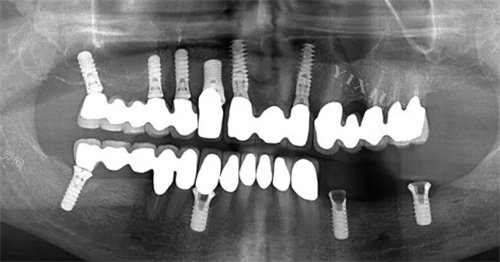

全口种植牙是针对牙齿全部缺失患者的一种修复方式,通过植入人工牙根来支撑固定假牙。与传统活动假牙相比,全口种植牙能提供更好的咀嚼功能和美观改善。这种修复方式通过将种植体植入牙槽骨中,待骨结合完成后安装连接基台和牙冠,然后实现牙齿功能的重建。

手术方案的选择也直接影响实际费用。All-on-4技术使用四颗种植体支撑全口假牙,价格区间为3-10万元;All-on-6技术使用六颗种植体增加稳定性,价格相应提高至6-12万元。此外,是否需要骨增量手术、即刻种植等附加治疗项目也会增加整体费用。

All-on-4技术是目前较为经济的全口种植方案,适合牙槽骨条件较好的患者。该技术通过四颗种植体支撑整排牙齿,上颌或下颌的费用约为3-10万元。这种方案手术时间相对较短,改善期也较快,但长期稳定性略逊于使用更多种植体的方案。

All-on-6技术比All-on-4多使用两颗种植体,提供更好的支撑力和稳定性,尤其适合咀嚼力较大的患者。价格区间为6-12万元,比All-on-4高出约30%-50%。对于牙槽骨条件较差或对咀嚼功能要求较高的患者,这种方案更为适合。

传统全口种植通常需要植入8-12颗种植体,价格可达15-30万元。这种方案虽然费用更高,但提供了更接近天然牙的咀嚼感受和长期稳定性,适合预算充足且追求良好结果的患者。